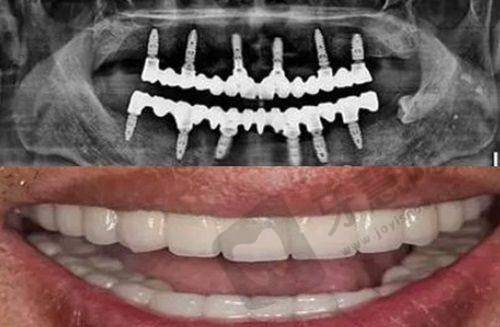

除了便捷的地理位置和交通条件外,重庆臻时代口腔更值得选择的原因在于其专精的医疗团队和精良的设备。门诊部拥有经验多的口腔骨干医生,在种植牙、牙齿矫正、牙齿美白等领域都有特别深造诣。

同时,门诊部采用的都是国内外精良的医疗设备,确保诊疗过程的精细和安心。在消毒方面更是严格遵循国内标准,让患者能够安心就诊。